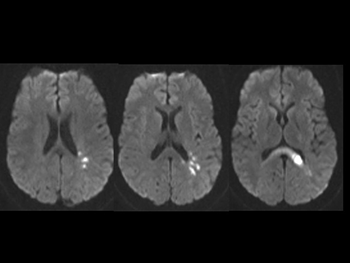

In the 2000s, the Shaywitzes conducted a series of studies. They compared brain activity in volunteers as they read. Some had dyslexia. The researchers scanned all of their brains using functional magnetic resonance imaging (fMRI). This tool measures blood flow during a task. Brain areas with the most blood flow tend to be the most active.

The researchers pinpointed several areas that turn on in normal readers. The most important two areas are in the back of the brain on the left side. The first is in the parieto-temporal (Puh-RY-eh-toh TEM-poh-rul) region. This area does the job of breaking a word into its sounds. The second area is in the occipito-temporal (Ah-SIH-pih-toh TEM-poh-rul) region. This is where the brain stores the appearance, sounds and meanings of words. This region, sometimes called the word-form area, “is critical for skilled and fluent reading,” explains Bennett Shaywitz. It allows readers to quickly identify words without sounding them out.

Finally, readers also use an area in the front, right side of the brain. It’s called Broca’s (BRO-kahs) area. The French neurologist Paul Broca discovered that this region allows a person to speak. Most people with dyslexia rely almost entirely on this speech region to read, the Shaywitzes showed. The two key areas in the back of the brain don’t do their job. The Shaywitzes called this brain activity pattern the “signature” of dyslexia.

Many other research groups performed similar studies. And they got the same results. They have even tested readers of different languages. Such work has helped scientists and teachers better understand dyslexia. But fMRI isn’t a good tool for finding out if someone has the condition. The pattern of brain activity that indicates dyslexia is not clear enough in an image of a single brain. The data are too complicated, says Sally Shaywitz. To see the pattern, researchers must combine together the data from many brains.